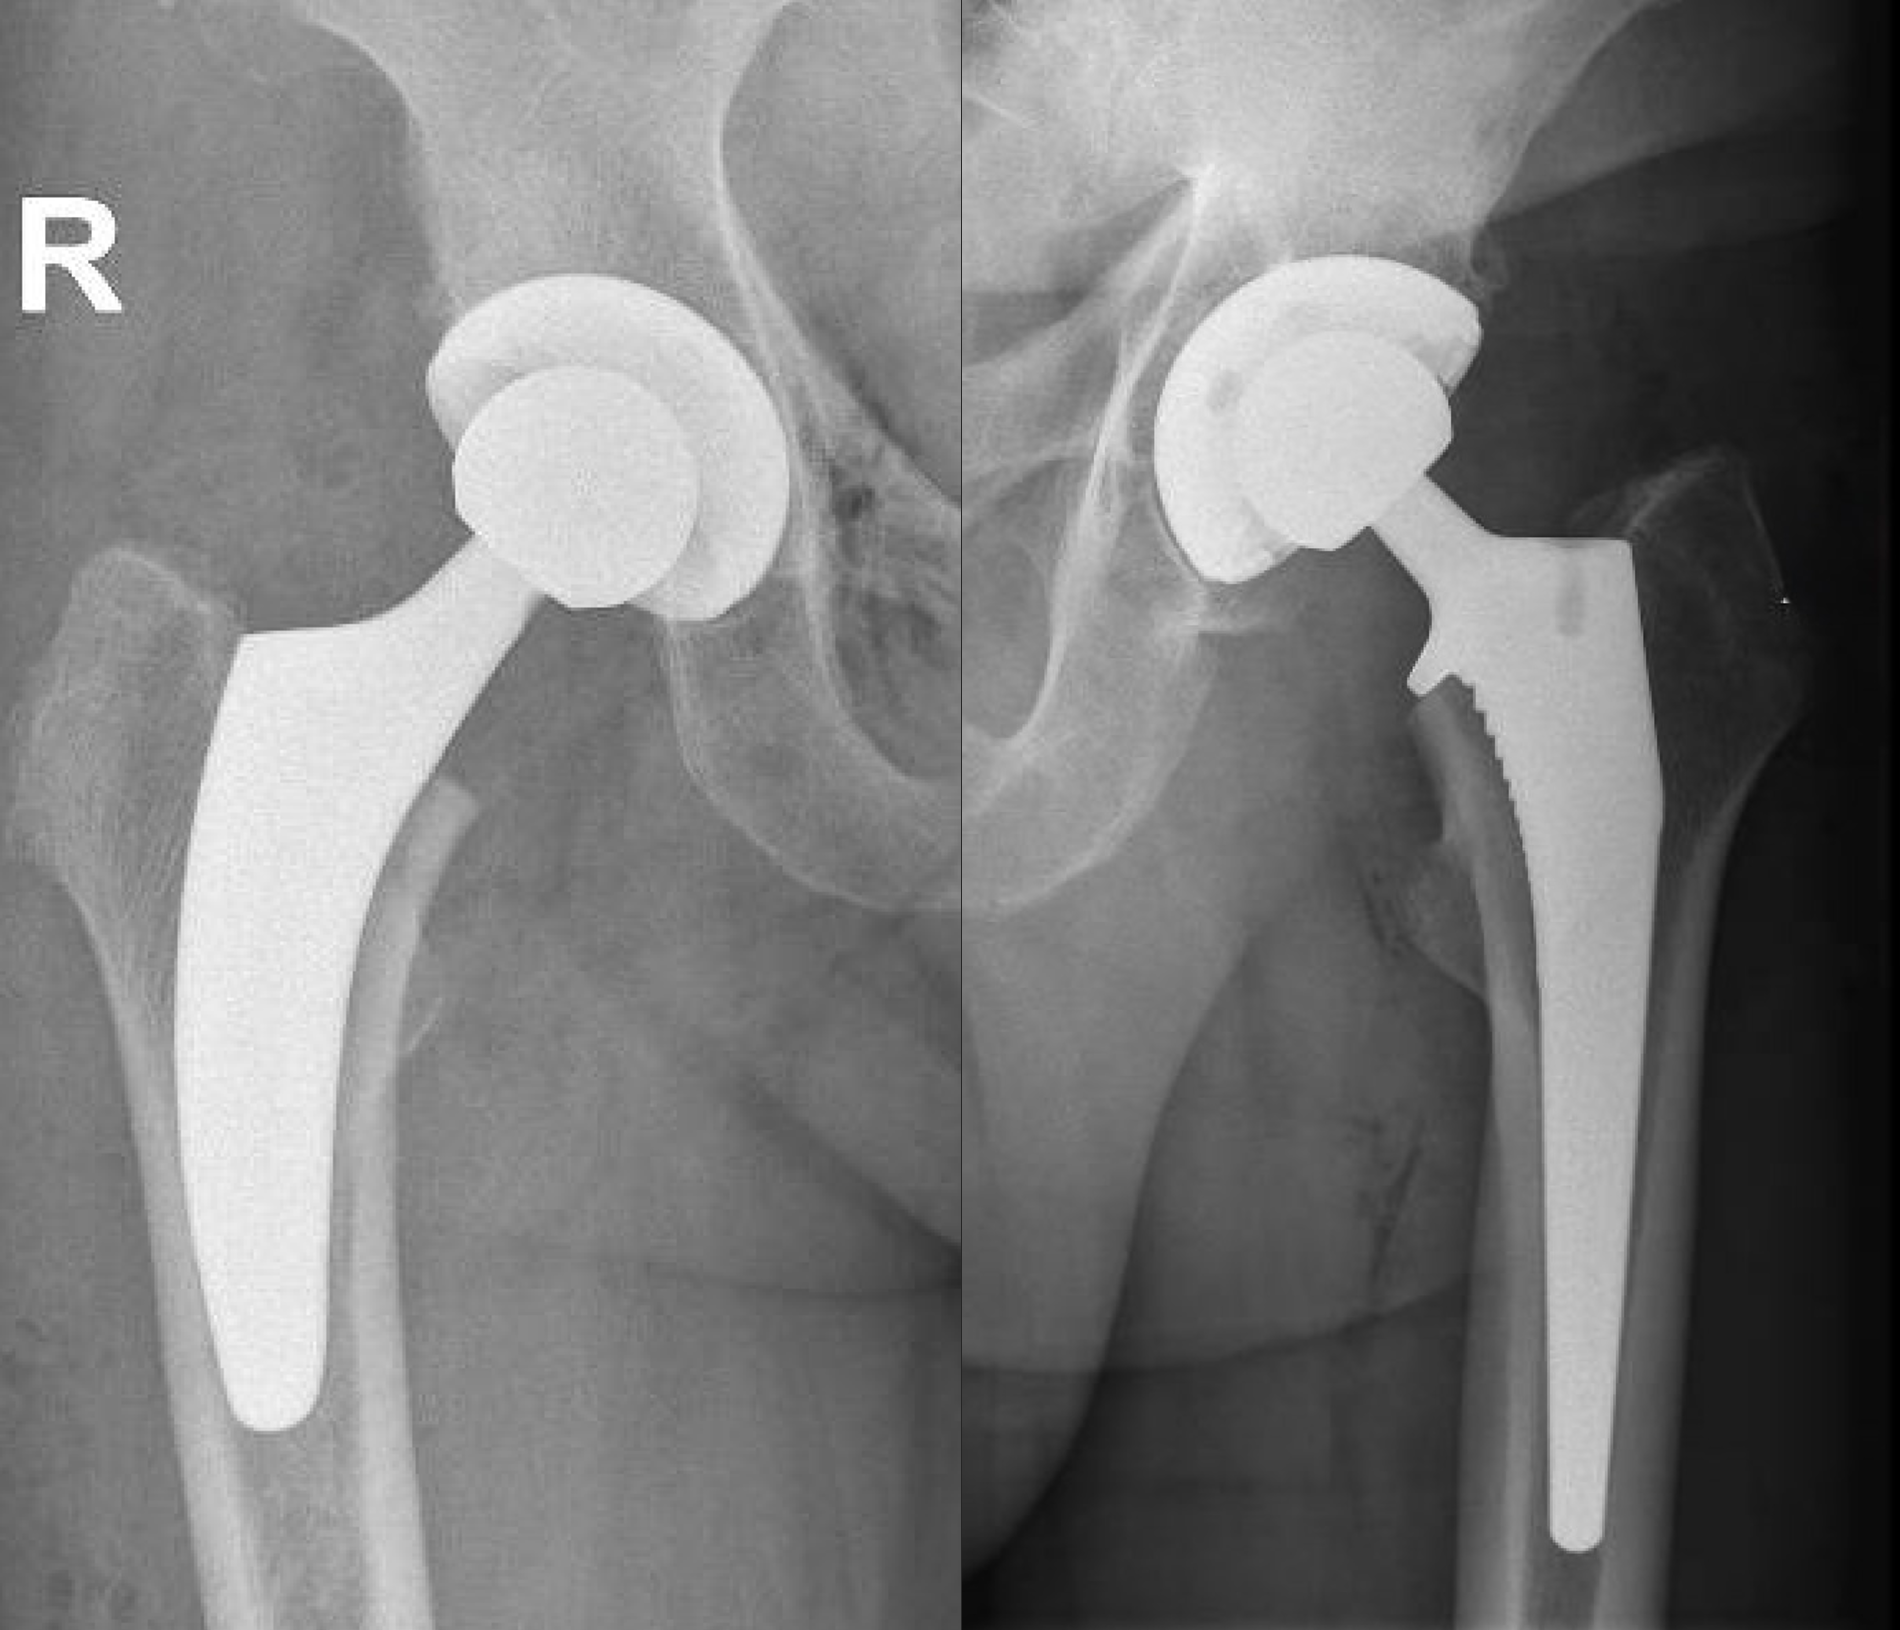

Bij de totale heupprothese-operatie wordt de versleten heup vervangen door een kunstgewricht.

Zowel de kom als de bol worden vervangen door een implantaat.

De nieuwe heupkom is gemaakt van een titaniumlegering. De binnenbekleding van de heupkom bestaat uit polyethyleen (zeer slijtvast medisch plastic).

De heupkop wordt vervangen door een metalen steel (titanium of kobalt-chroom) in het bovenbeen, waarop een kopje van keramiek wordt geplaatst.

Totale heupprothese